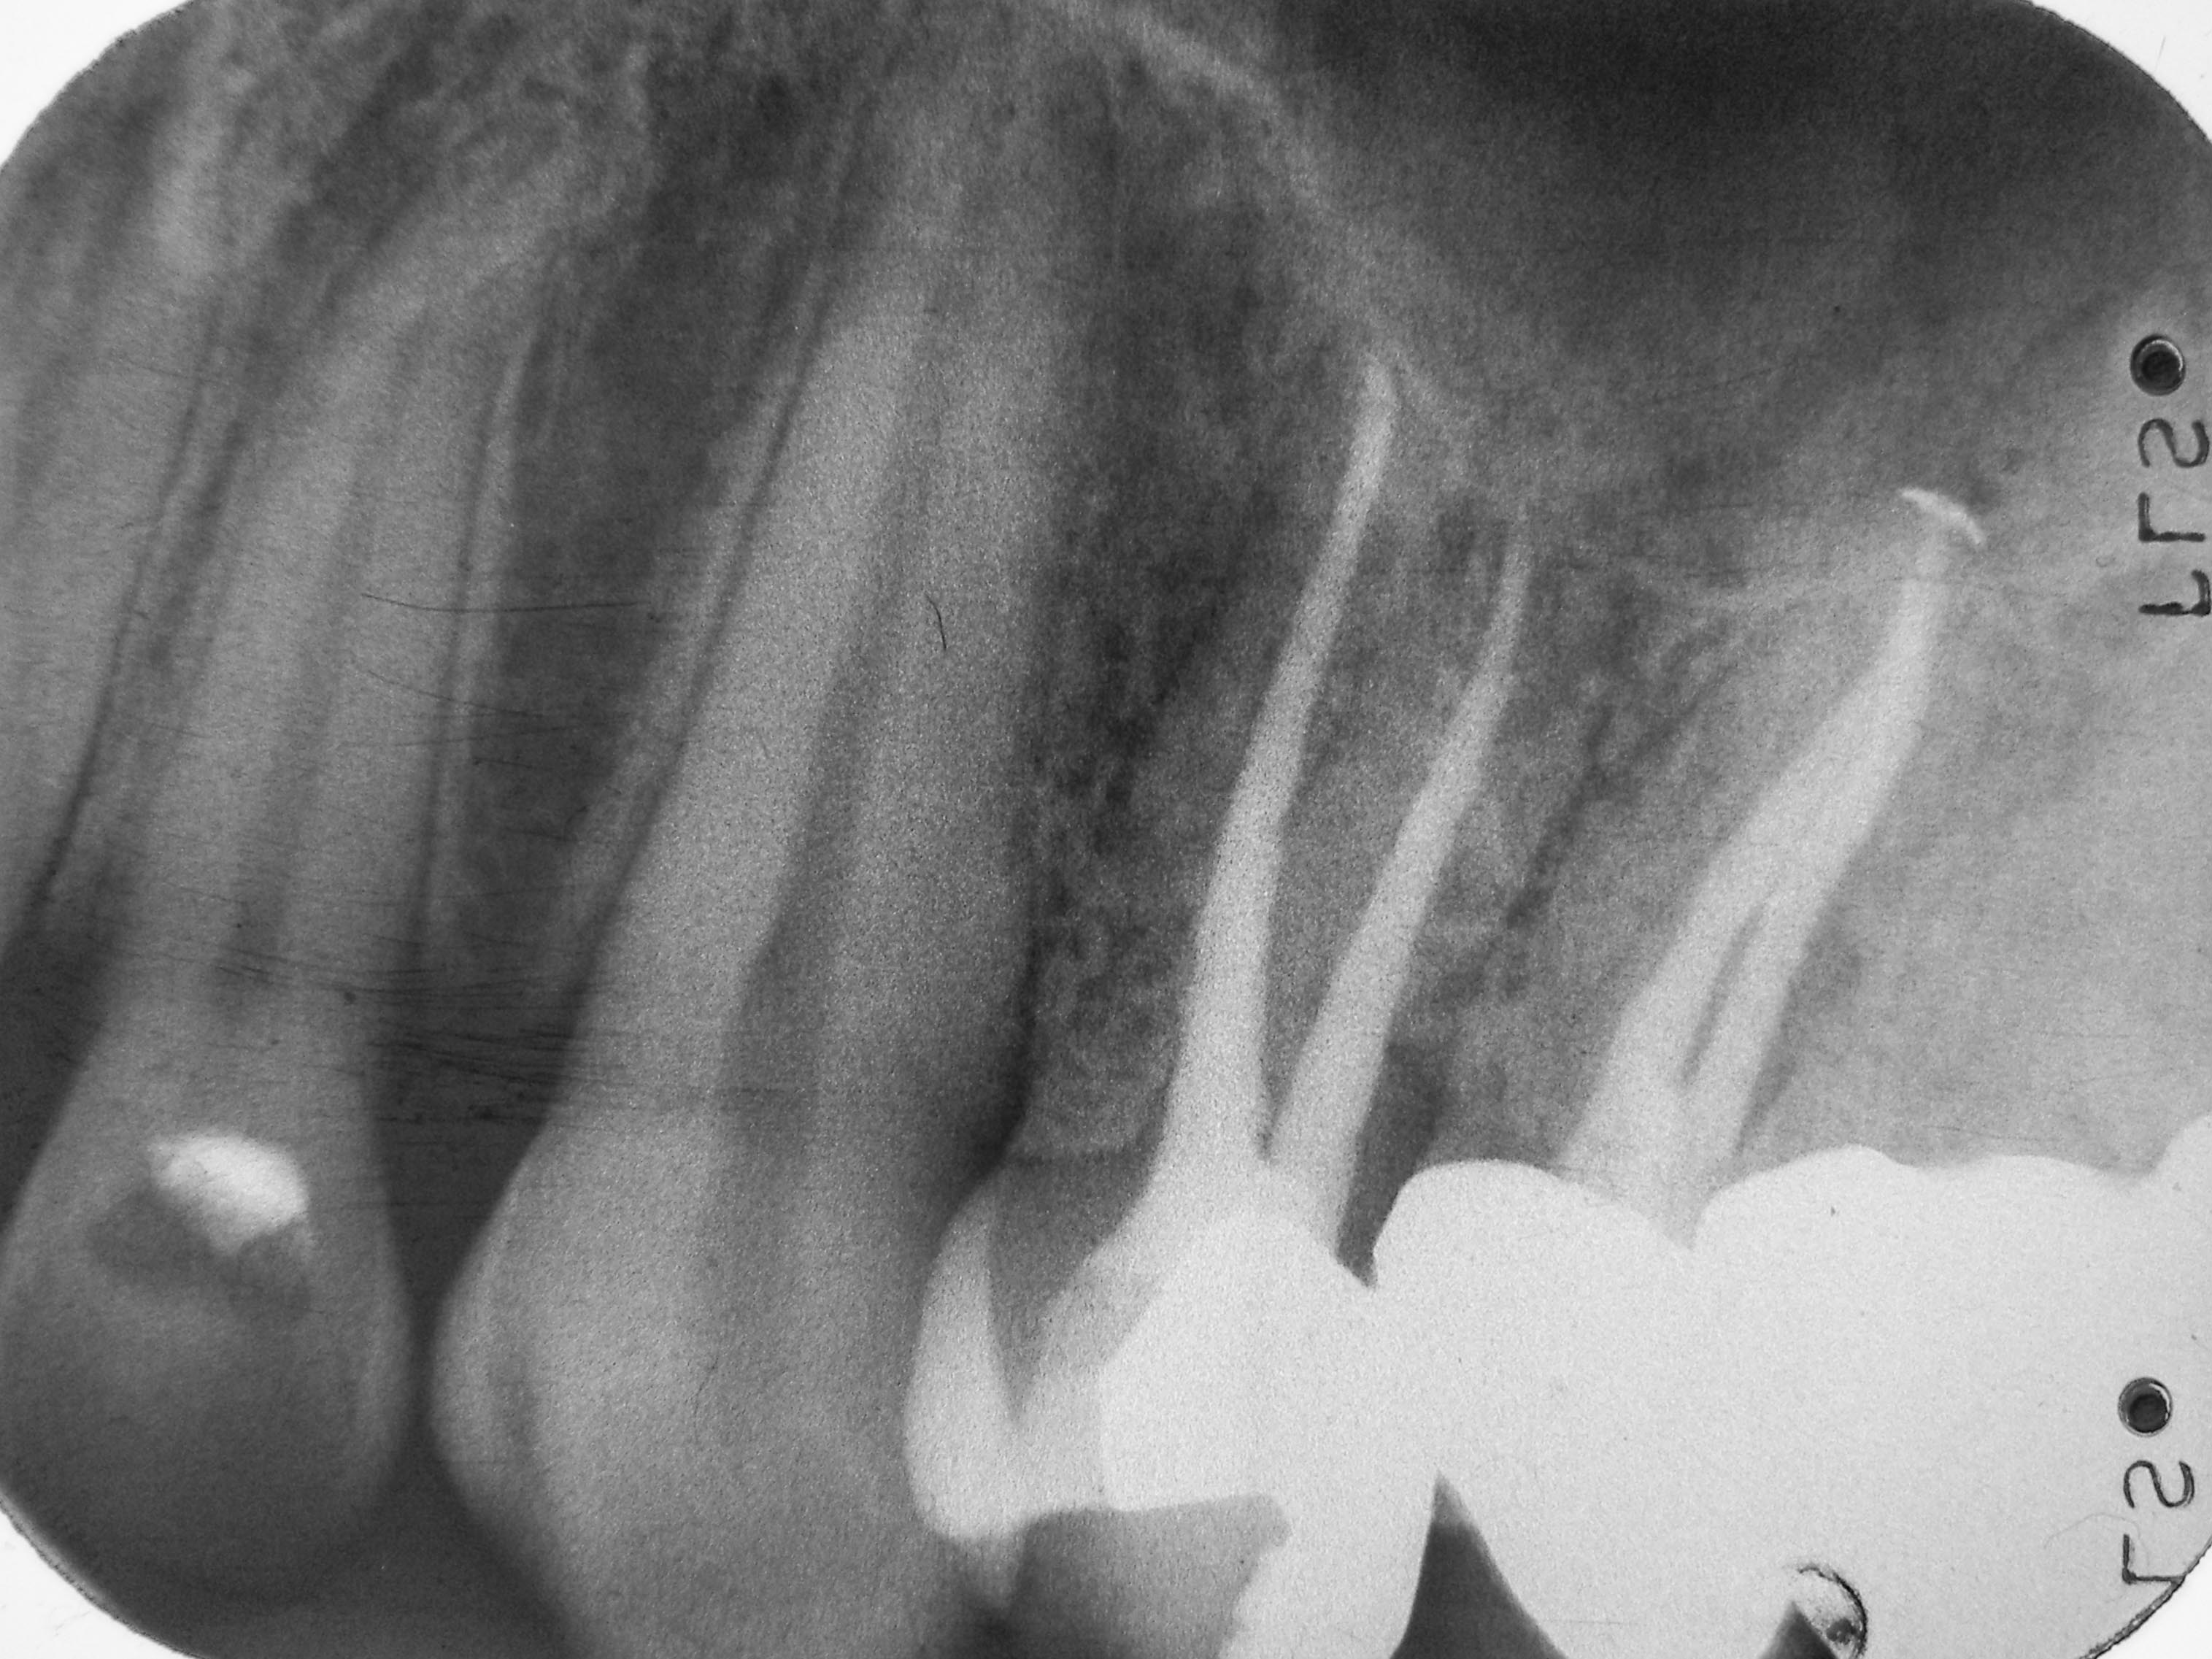

24 WF- Kontrolle Veröffentlicht 5. November 2013 am 3031 × 2273 in „Chapeau“ oder der Wirt und die Wette 24 WF- Kontrolle 2001